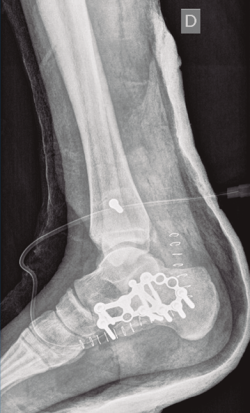

Figura 1. Luxación del astrágalo en mortaja tibioperonea, fractura maléolo peroneo y espacio subperoneo ocupado por calcáneo.

Se trata de un varón de 19 años que ingresa en reanimación tras precipitarse desde una altura de aproximadamente 10 metros. El paciente presenta una fractura estallido de L3 con afectación del canal medular junto con una fractura del vértice inferior de L4, así como una fractura luxación de calcáneo, asociada a una fractura del maléolo peroneo y del maléolo tibial posterior (Figuras 1 a 6) diagnosticadas mediante TC total body (por eso no se dispone de radiografías simples al momento del ingreso). Como podemos comprobar, se trata de una fractura de doble trazo de tipo hundimiento/depresión de la carilla articular (Figuras 5 y 6).

Figura 5. Fractura maléolo peroneo, luxación astrágalo, fractura de doble trazo en calcáneo.

Figura 7. Radiografía lateral de pie y tobillo; se evidencia fractura de calcáneo y de maléolo tibial posterior.